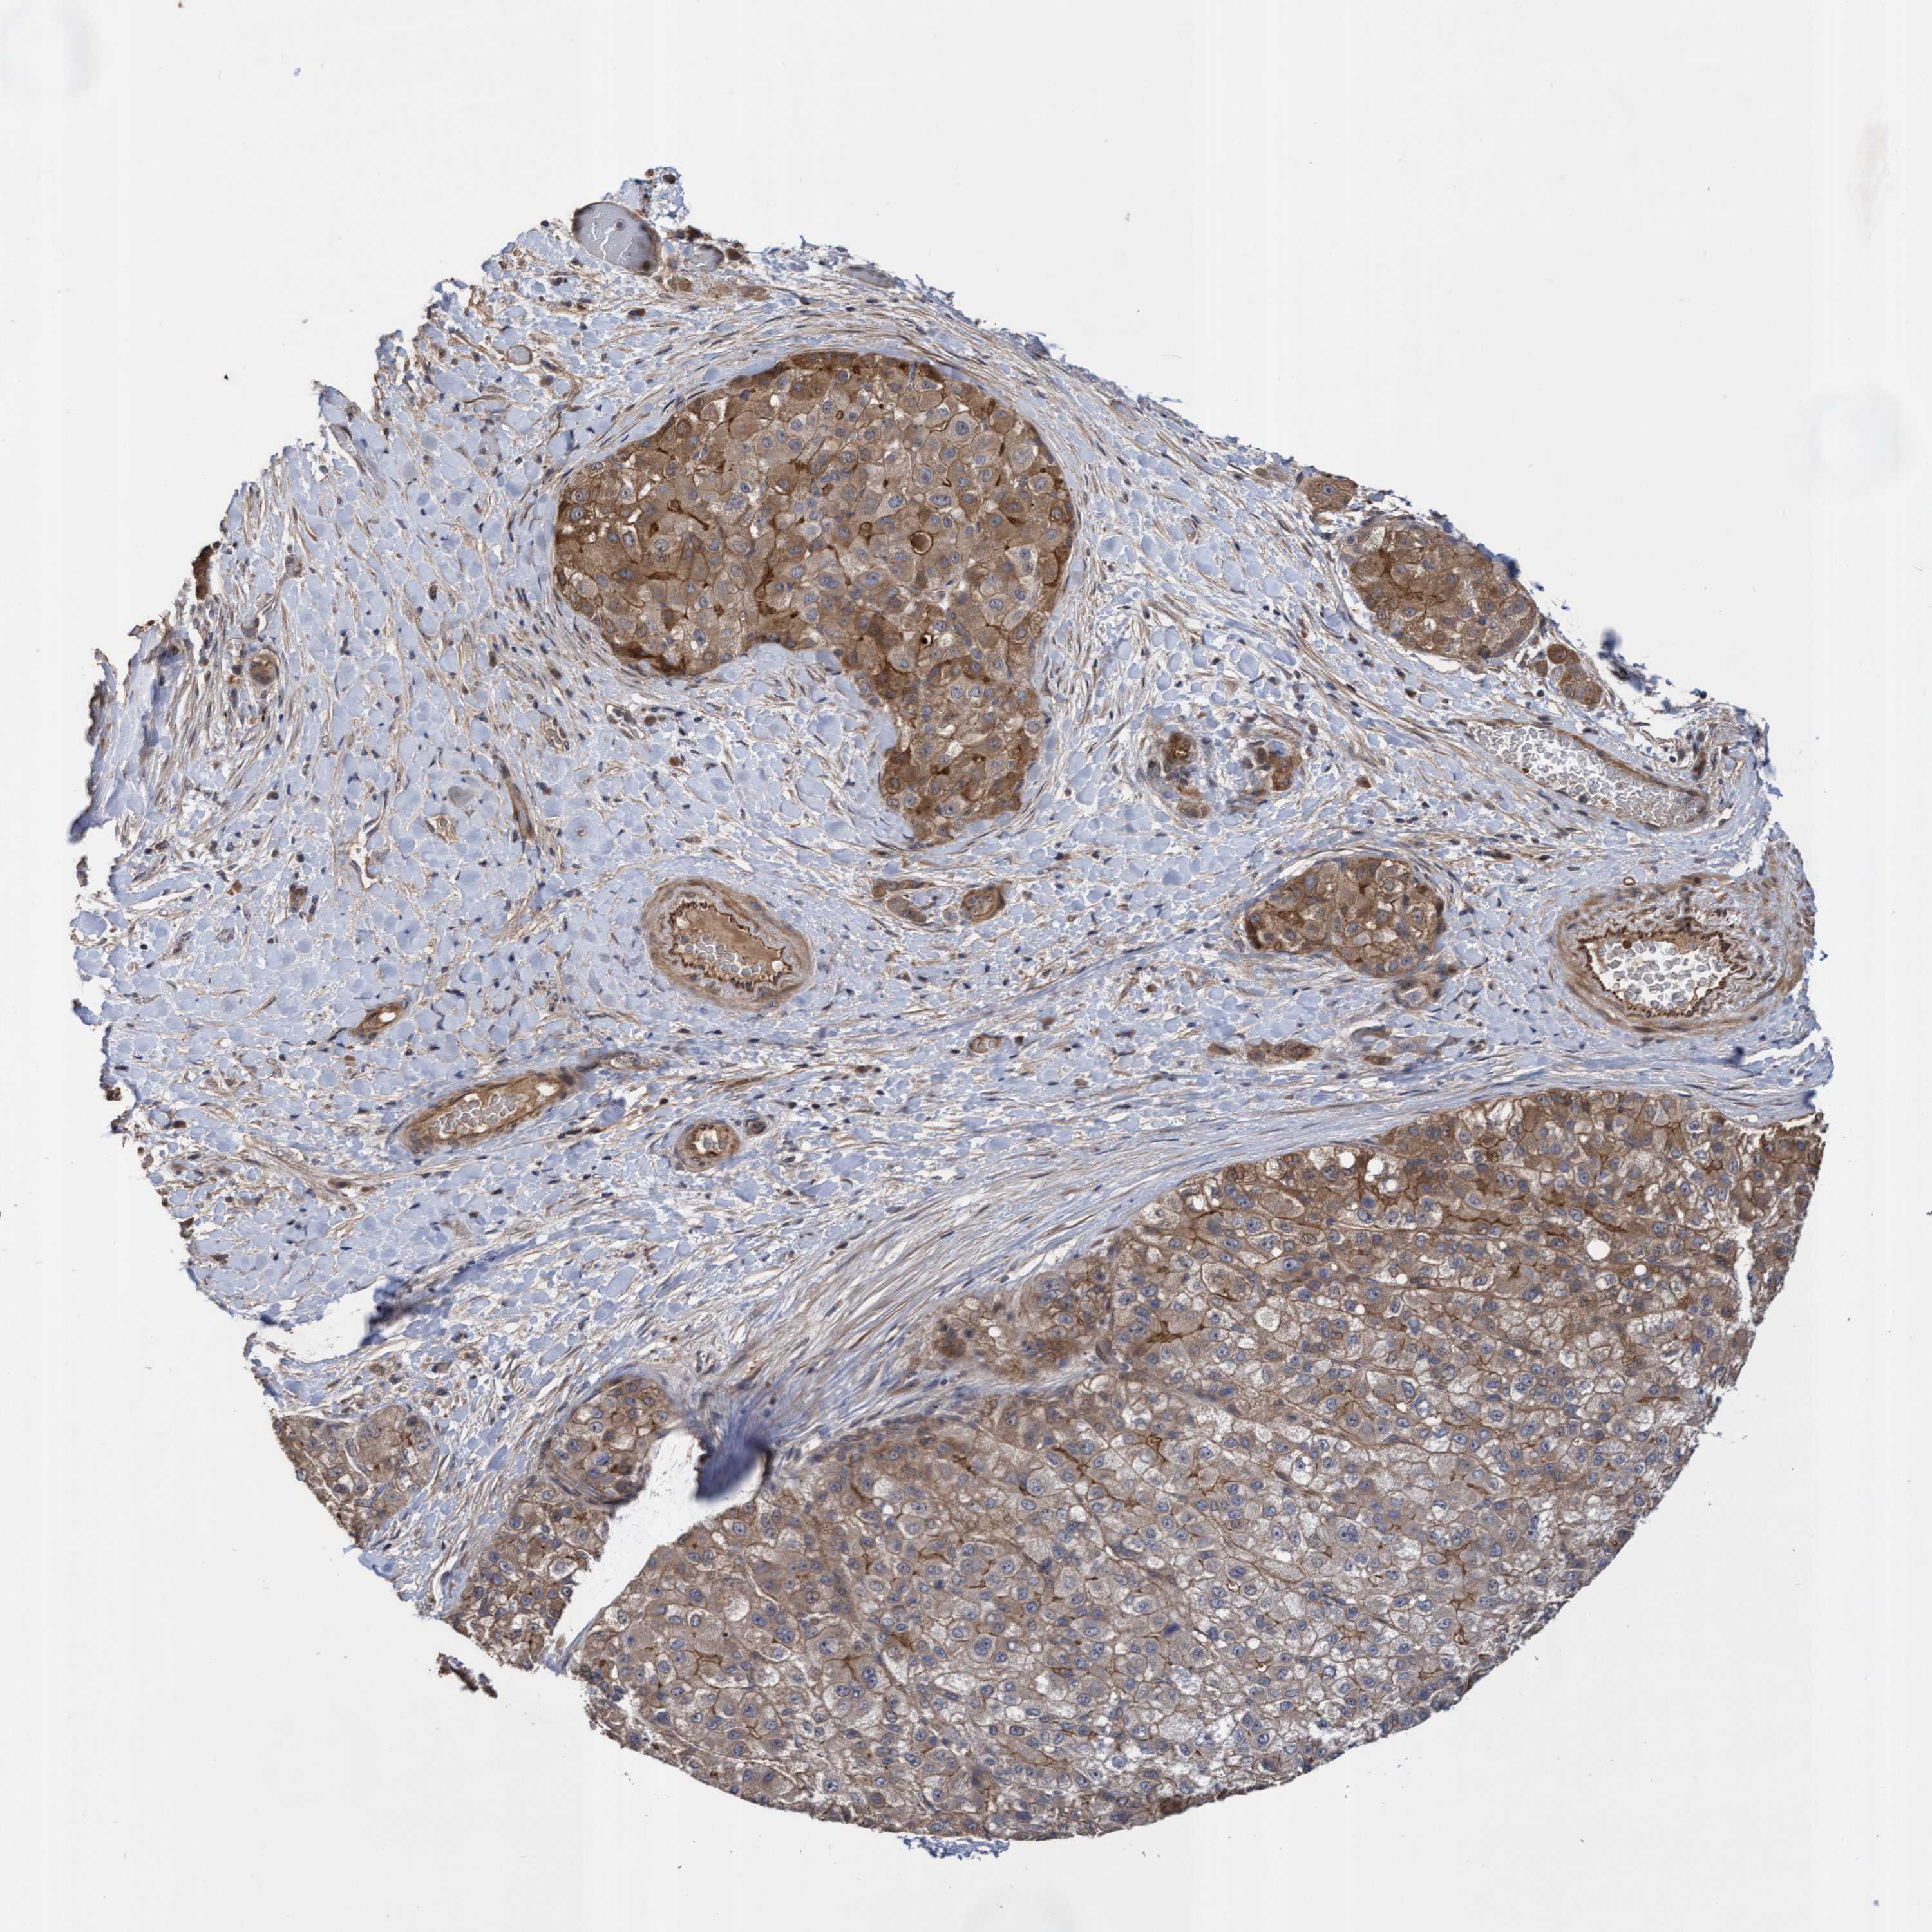

LIVER CANCER - Protein expressioni

A mouse-over function shows sample information and annotation data. Click on an image to view it in a full screen mode. Samples can be filtered based on level of antibody staining by selecting one or several of the following categories: high, medium, low and not detected. The assay and annotation is described here.

Note that samples used for immunohistochemistry by the Human Protein Atlas do not correspond to samples in the TCGA dataset.

Antibody stainingi

Antibody staining in the annotated cell types in the current human tissue is reported as not detected, low, medium, or high, based on conventional immunohistochemistry profiling in selected tissues. This score is based on the combination of the staining intensity and fraction of stained cells.

Each image is clickable and will lead to virtual microscopy that enables deeper exploration of all samples and also displays staining intensity scores, fraction scores and subcellular localization as well as patient and tissue information for each sample.

Antibody HPA019033

Antibody HPA019167

Staining

High

Medium

Low

Not detected

Intensity

Strong

Moderate

Weak

Negative

Quantity

>75%

75%-25%

<25%

None

Location

Nuclear

Cytoplasmic/membranous

Cytoplasmic/membranous,nuclear

Cholangiocarcinoma

Carcinoma, Hepatocellular, NOS